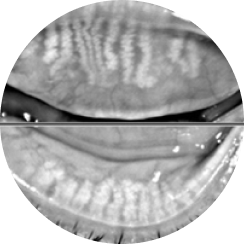

• 세극등 현미경 검사

세극등 현미경 검사

눈물막 / 마이봄샘 기능 / 안검, 결막 염증

등등의 각막의 상태를 상세히 검사합니다.